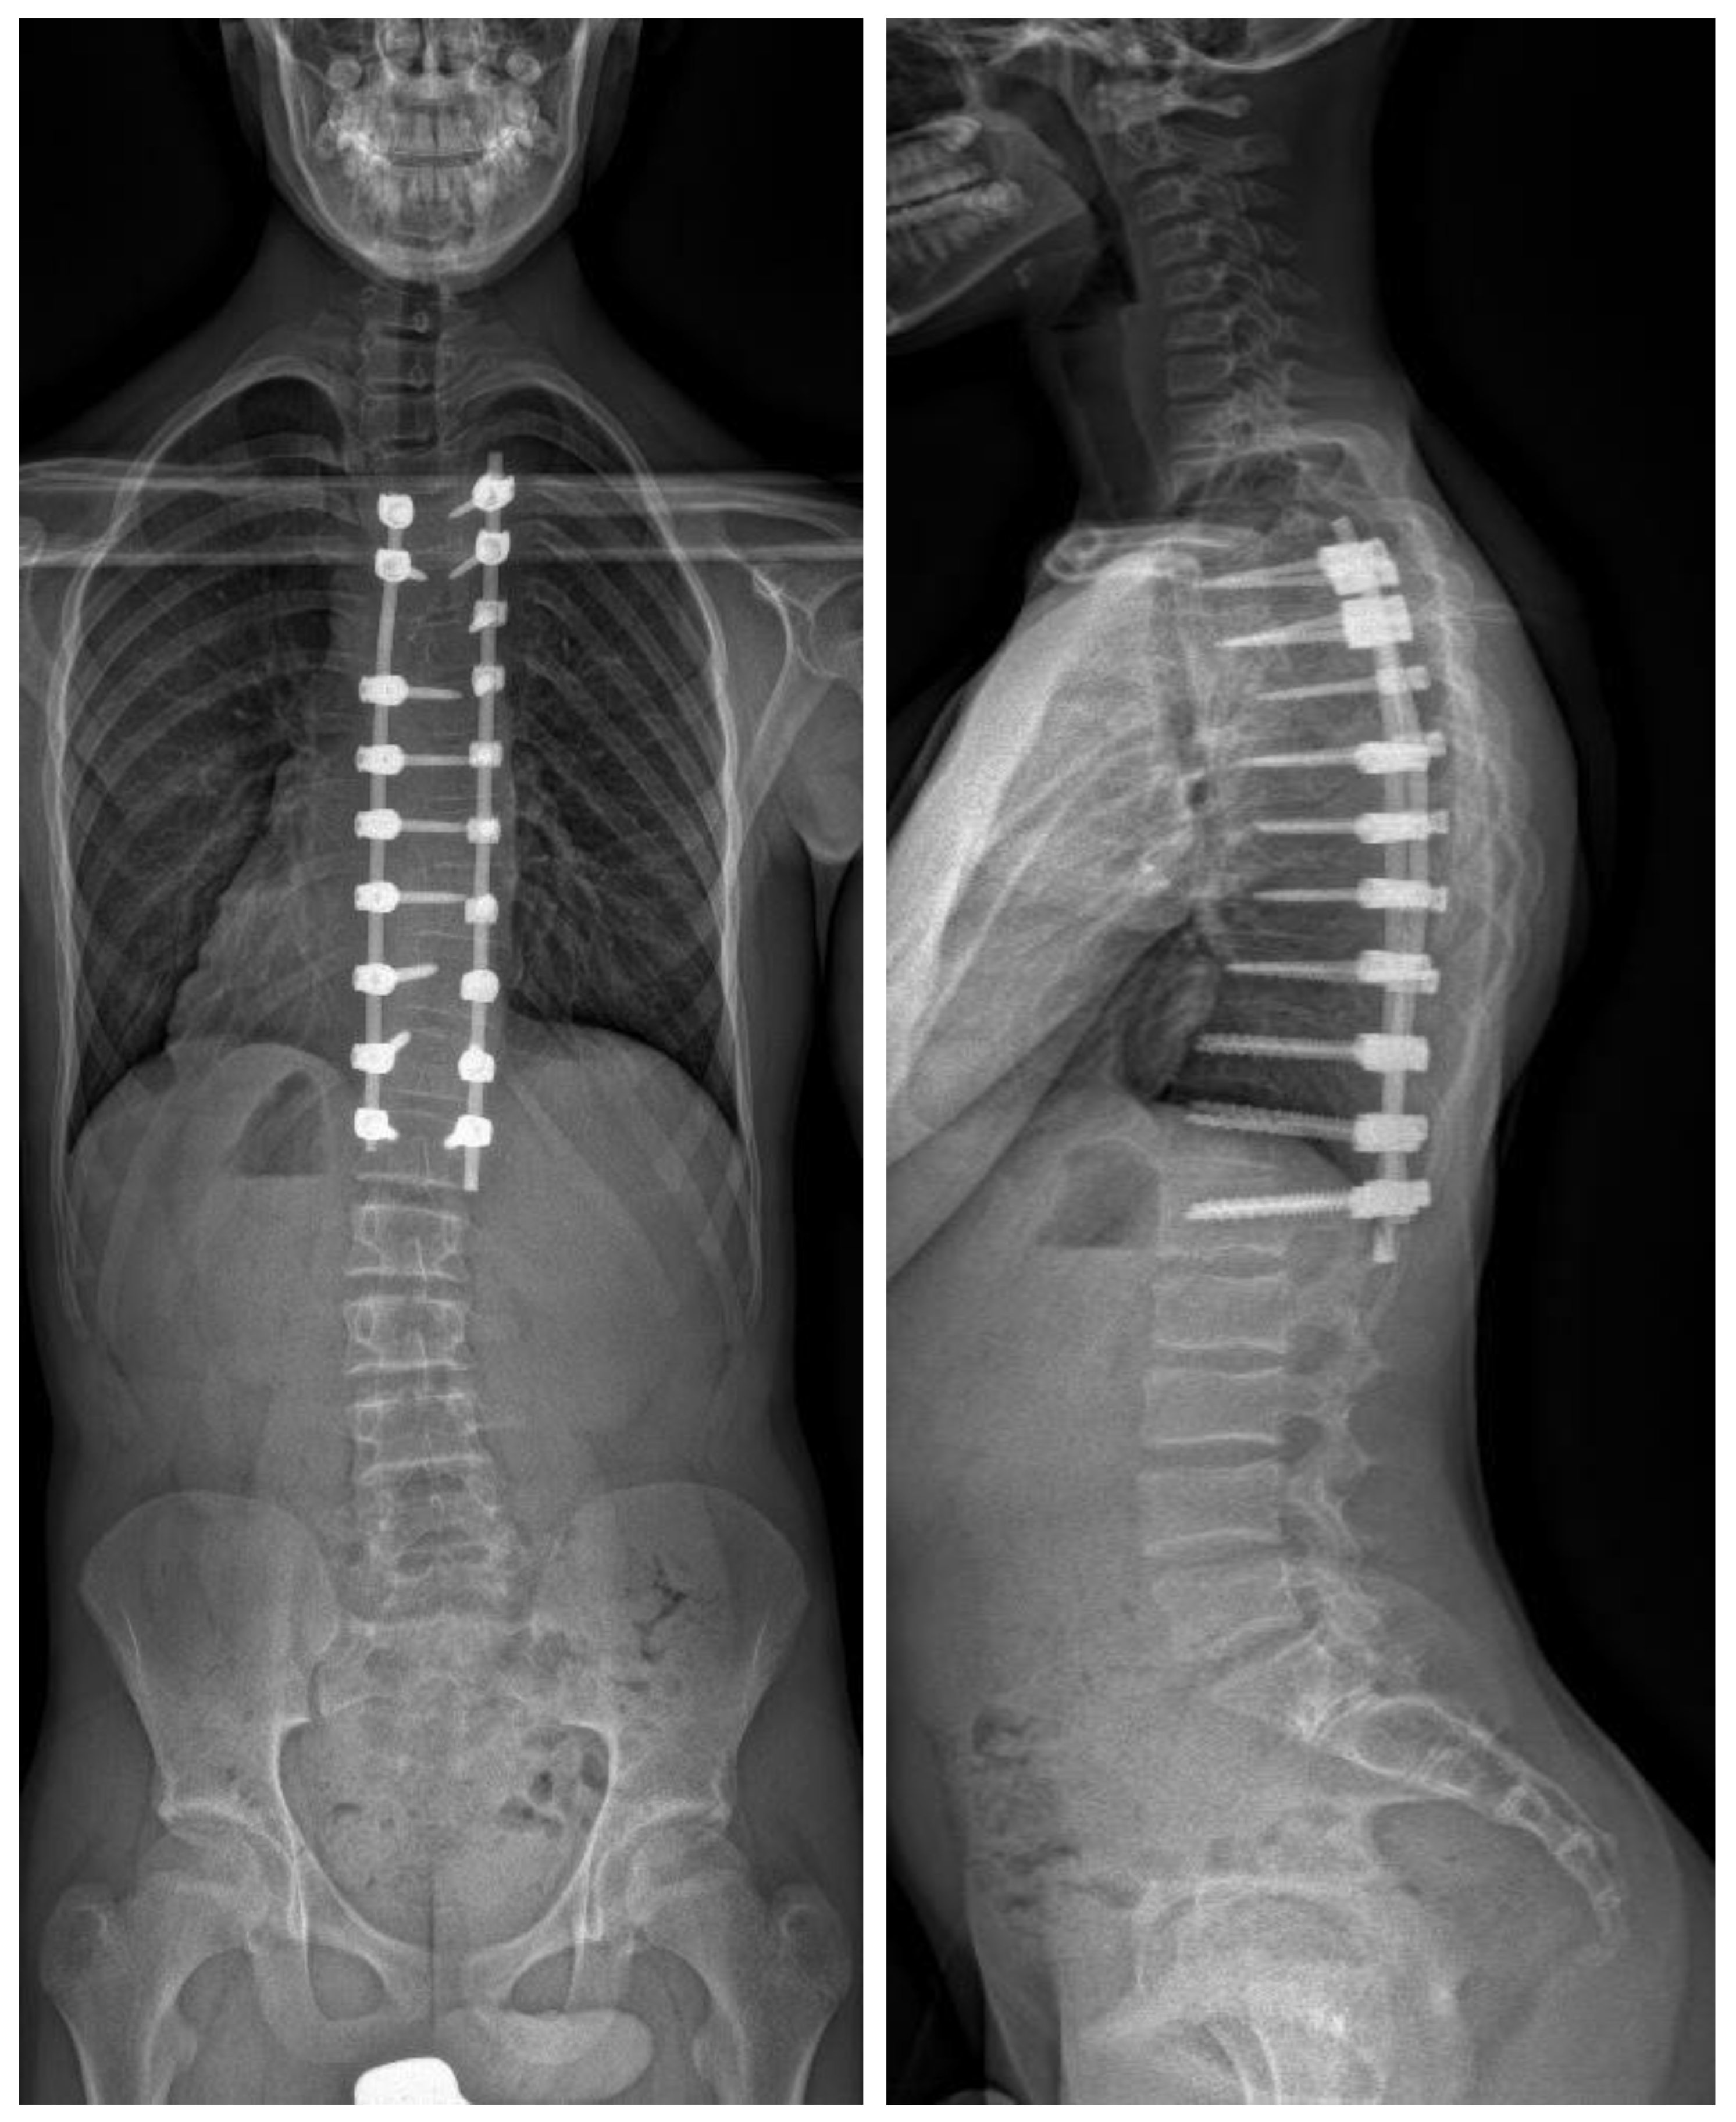

Figure 2.

Biplanar radiograph of the same patient after posterior instrumented fusion using freehand technique. The intraoperative DAP was 638.2 mGy/cm2.